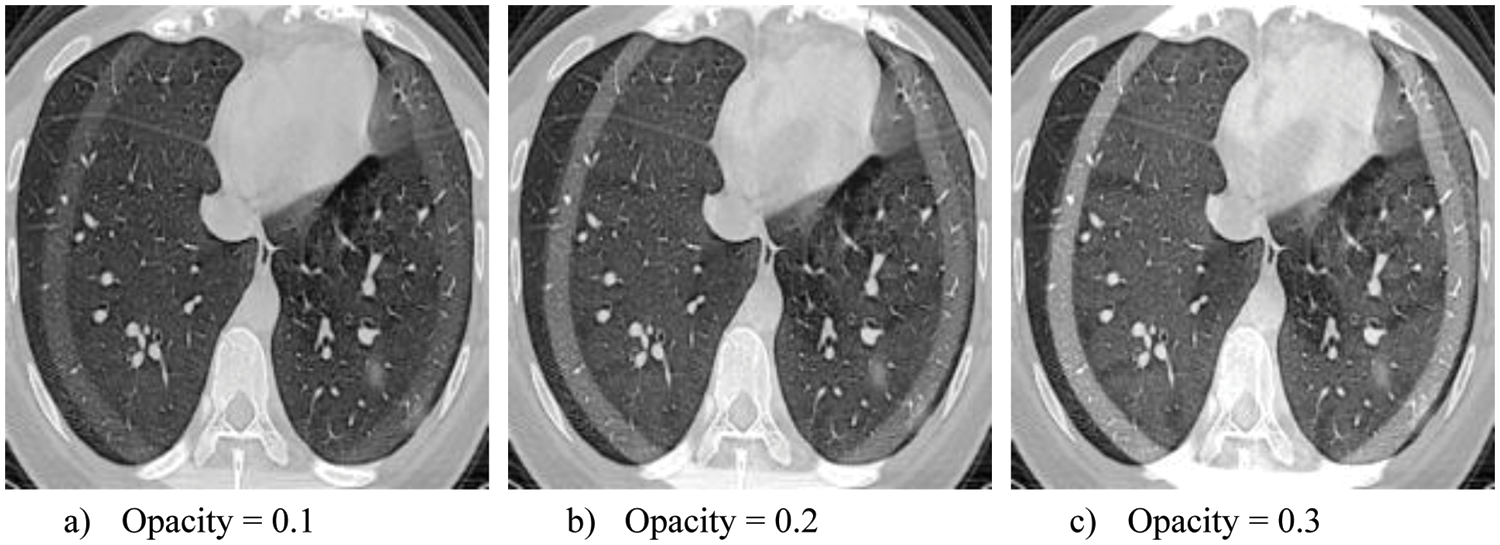

4.2 Alpha Fusion Protuberant Images

In this research work, alpha fusion attack images are generated and passed to the trained model for confusing it to predict wrong labels. Alpha fusion attack is more lethal if we tune its most important parameter, opacity, by changing its value. It affects the model violently, making its defense more complex. The generated protuberant images with three opacity variants are shown in Fig. 5.

Figure 5: Variant of attack images

The classification results gained from different classifiers before the adversarial attacks are illustrated in Figs. 5a to 5d. It shows the F1 score achieved by various classifiers on test data. All the classifiers are fine-tuned and validated on the same test data. As you can see pre-trained model performs slightly better than CNN modified LSTM model (CNN-MLSTM). Figs. 5e to 5h present the classification of different models after the alpha fusion attacks with three variants of opacity (0.1, 0.2, and 0.3). Fig. 5h elucidates the F1 score of various classifiers, with opacity 0.1 Alpha Fusion Attack affecting the F1 score and accuracy by almost 30%. As you can see, the CNN model effect more than other models; on the other hand, CNN-MLSTM and Resnet50 achieve the same accuracy. The RCNN model got 61% accuracy. The F1 score of various classifiers, with opacity 0.2 Alpha Fusion Attack, badly affects the results, i.e., almost drops by 42%. However, somehow RCNN model performs a little better than other models, and CNN-MLSTM and Resnet50 models perform almost the same. It shows the F1 score of various classifiers, with opacity 0.3 Alpha Fusion Attack badly affect the results F1 Score almost drop by 50%. Highly trained models perform so much less than expected. In this section, CNN-MLSTM is again tuned to achieve better results. The CNN-MLSTM and RCNN perform almost the same. As in Fig. 6a, its shows the accuracy value of all deep learning accuracy values before the attack in CNN, it achieves 93%. Fig. 6e shows the accuracy after the attack when the attack opacity level is 0.1 CNN accuracy down to 58%, at 0.2 accuracies down to 41% and at 0.3 its drop to 22%. In Fig. 6b before the attack, the CNN F1 score is 95.55%, but in Fig. 6f, after an attack with an opacity value of 0.1, it drops to 57, when the attack value is 0.2, its score drops to 40.5 and when the opacity value is 0.3 CNN score drop to 21.8. For precision, CNN before attack value is 96.25 in Fig. 6c wheres it decreases to 59 with the opacity value is 0.1 after the attack in Fig. 6g. It further decreases to 41 and 21.5 for the with a opacity value of 0.2 and 0.3, respectively. Fig. 6d shows the before attack value for Recall where CNN value is 95.4. Fig. 6h shows the results after attack where the recall value of CNN decreases to 56, 39.9 and for at opacity value 0.1, 0.2 and 0.3 and with value 0.3, respectively.